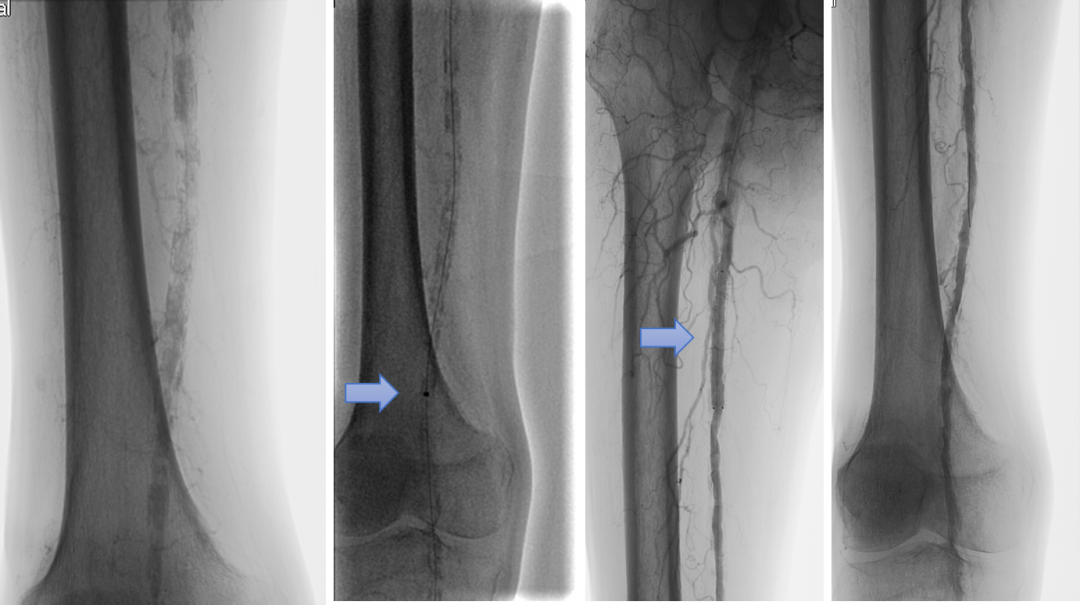

病例三:重度钙化--一期减容治疗

患者为多节段长段钙化(PACSS 4级)。直接采用激光减容(Turbo-Elite 2.3mm),减容后局部出现明显弹性回缩伴夹层,最终在局部植入短支架(Innova 6mm×80mm)解决问题。整个病变长度20cm,仅以短支架处理关键部位,最大限度减少支架植入。